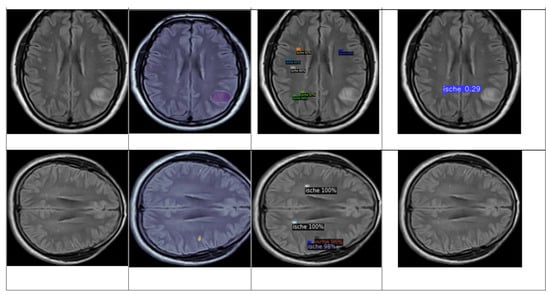

4.3.1. YOLOv8 Model for Detection and Classification

4.3.2. DETECTRON2 Model for Detection and Classification

- The total loss (‘total_loss’, mean value 0.300) indicates that the model has learned the essential features needed for classification and stabilization with minor fluctuations.

- The box regression loss (‘loss_box_reg’, mean value 0.072) decreases as the model learns to predict better-bounding boxes after stabilizing at a low value. This indicates that the model has become proficient in predicting bounding box coordinates.

- The classification loss (‘loss_cls’, mean value 0.030), through the pass of iteration, decreases and stabilizes, which suggests the model has learned to classify most of the lesions correctly.

- The mask loss (‘loss_mask’, mean value 0.154), shows decreasing and stabilizing values, which indicate a consistent performance in mask predictions.

- The RPN classification loss (‘loss_rpn_cls’, mean value 0.007) indicates a stabilization, which means that the region proposal classification task model has learned to propose regions accurately.

- The RPN localization loss (‘loss_rpn_loc’, mean value 0.029) stabilizes at a low value, which indicates the model’s proficiency with the localizing regions.

- The classification accuracy (‘fast_rcnn/cls_accuracy’ and ‘mask_rcnn/accuracy’) shows improvement through the iterations and gets stabilization values of 0.98 and 0.93 for both accuracies, respectively, which means the model is classifying lesions correctly most of the time (fast_rcnn/cls_accuracy) and that the model has high accuracy in mask prediction (mask_rcnn/accuracy).